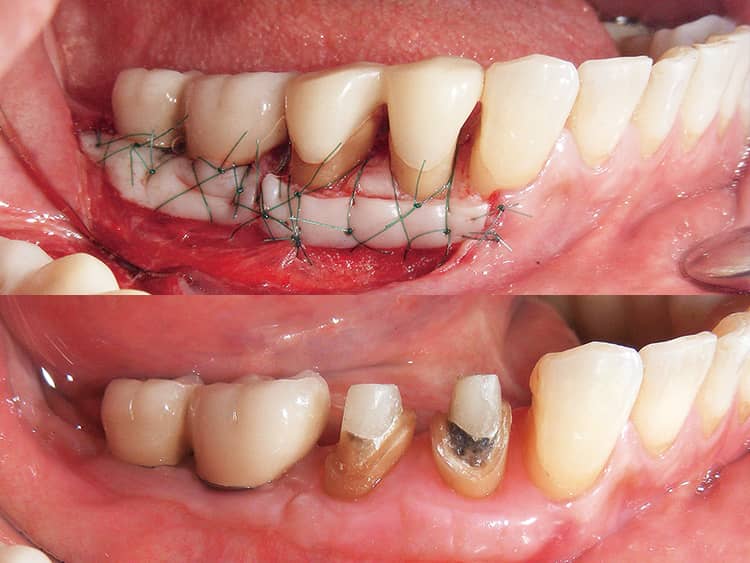

FPCは歯根破折を起こしにくいが、反面歯肉縁で水平性破折が発生しやすい。これは補強しているとはいえ、メタルに比べて曲げ強さが低いことに起因している。これを防止するために歯肉縁上歯質の獲得は非常に重要となる。この部分は咬合力を負担する役割を担っており、またフェルール効果を得るために必要だと考えられているためである。過去に発表された様々な文献をまとめると、少なくとも幅1mm、高さ1mm程度は必要と考えられ、その獲得のためにエクストルージョンや外科的歯冠長延長術などのオプションを持つことが重要である(図10、11)。

図10 エクストルージョンを応用した例。隣在歯と調和のとれた生理的な歯周組織を獲得するために歯周外科処置の併用が必要となる場合が多い。

図11 歯冠長延長術と遊離歯肉移植術を同時に行った例。このケースでは新たに2mmの歯肉縁上歯質と質の高い歯周環境を獲得できた。